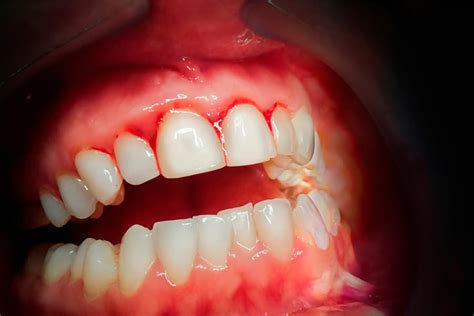

¿Te sangran las encías al cepillarte los dientes? Este es un problema común que puede indicar diversas afecciones, desde una simple inflamación hasta enfermedades periodontales más serias. Según un estudio publicado por GSK, el 40% de la población sufre problemas de encías. Es importante no ignorar este síntoma y buscar soluciones adecuadas para mantener una buena salud bucal.

Si sangran las encías es porque nos están avisando de la presencia constante de inflamación, muchas veces de causa bacteriana. Las encías sangrantes se producen cuando hay una alteración en el equilibrio de las bacterias de nuestra boca, sucediendo habitualmente por el acúmulo de placa.

La gingivitis es la causa más frecuente de sangrado de las encías. Esta enfermedad periodontal produce una inflamación de las encías y suele suceder por la acumulación de placa bacteriana entre los dientes. Si la gingivitis no se trata correctamente, puede derivar en una periodontitis, conocida popularmente como piorrea.